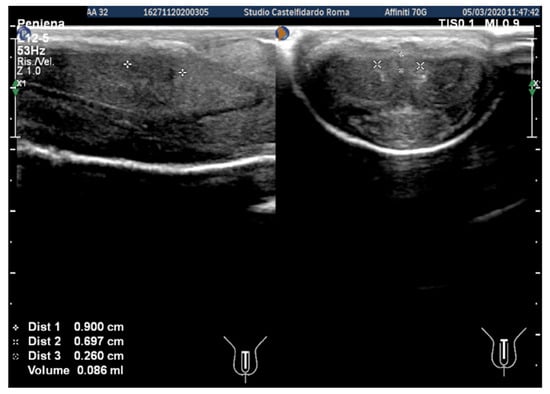

| 3 | 30 years | Left varicocele | Proximal third | (A) 12.2 × 11.2 × 2.81 mm volume = 203 mm3 (B) No plaque detected | (A) No penile deformation (B) No penile deformation | VAS score = 5 Pain disappeared after 4 months | 26 > 26 | 4 months | Orally: propolis 600 mg + bilberry 160 mg + silymarin 400 mg + ginkgo biloba 250 mg + vitamin E 800 IU/daily for 4 months + topically: diclofenac gel 4%/2× daily for 4 months Note: Penile injections not needed |